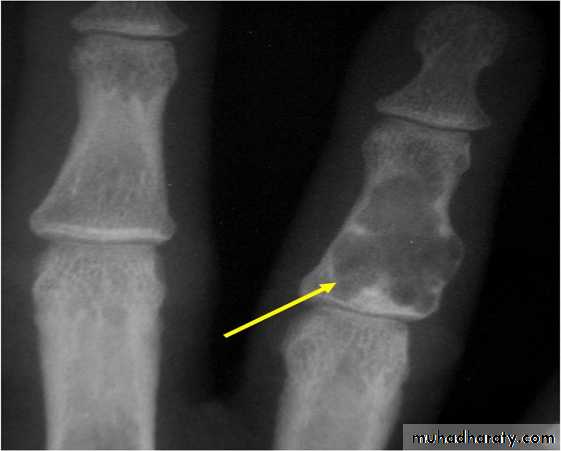

Solitary bone cyst:

Age: young adults & children.Site: long bones.

Findings: well-defined expanding lytic lesion.

A piece of cortical bone has broken off and descended through the serous fluid contained within the lesion and can be seen in the dependent portion of the lesion (arrow) as

a fallen fragment sign.

A fallen fragment sign is said to be pathgnomonic for

a unicameral bone cyst

Fallen fragment sign